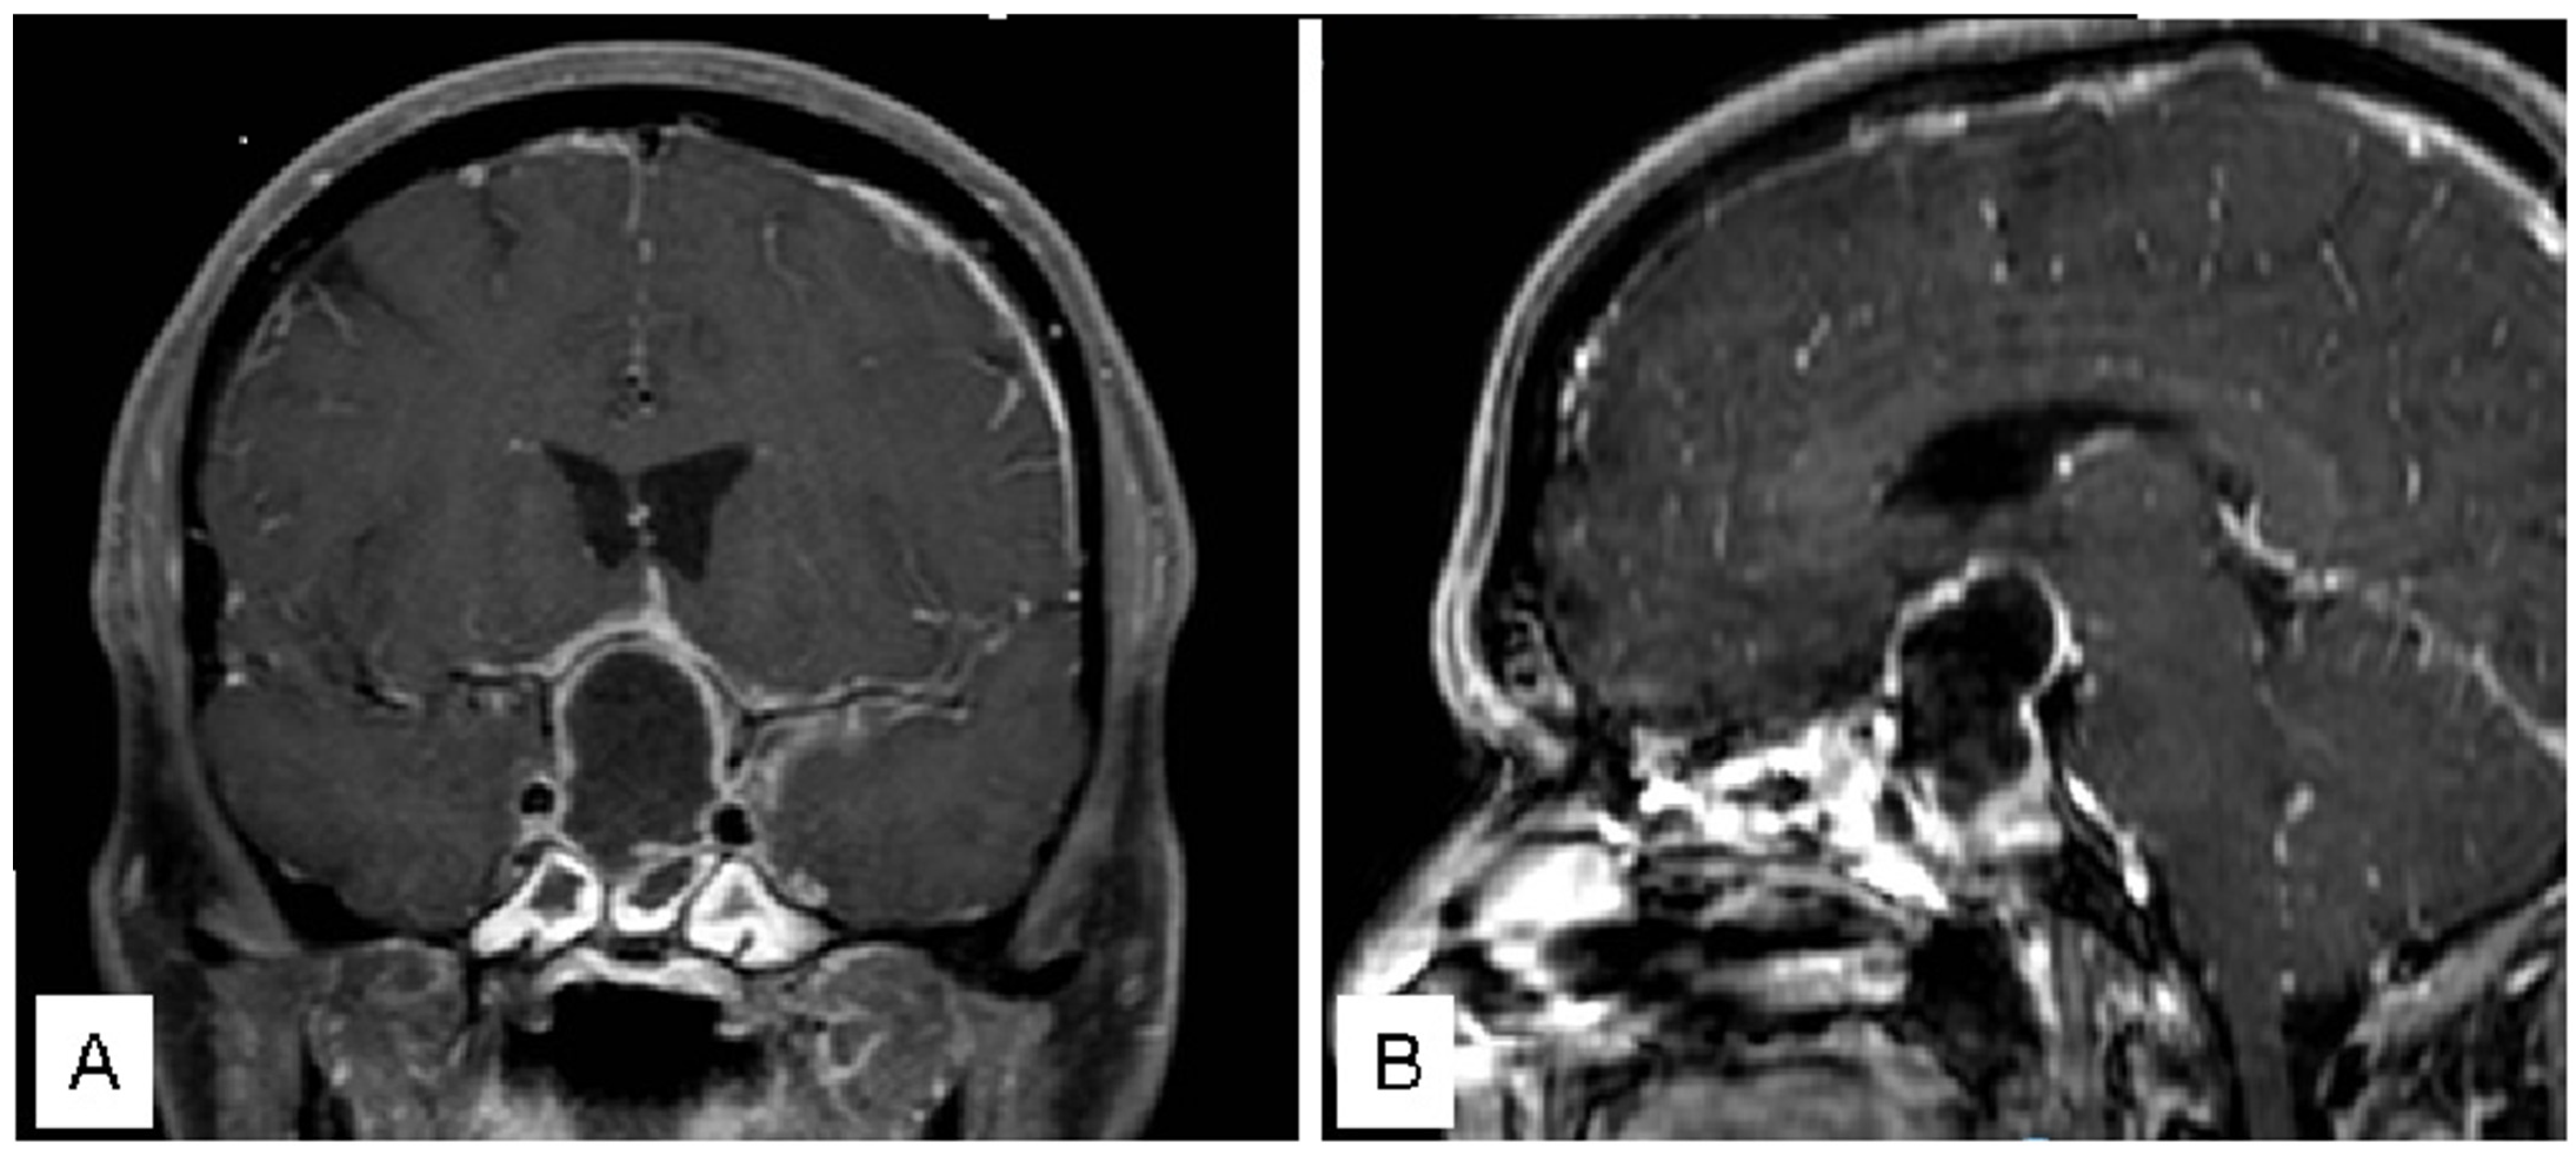

3.1.1. Case 1

3.1.2. Case 2

3.1.3. Case 3